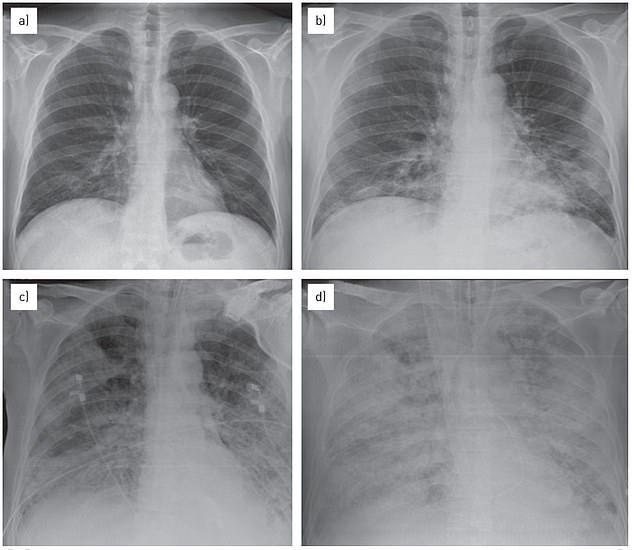

The above image pictures the lungs during 'white lung syndrome' or acute respiratory distress syndrome, which is diagnosed via the white spots or opaque areas appearing in the lungs. The above patient was a 57-year-old man in 2014